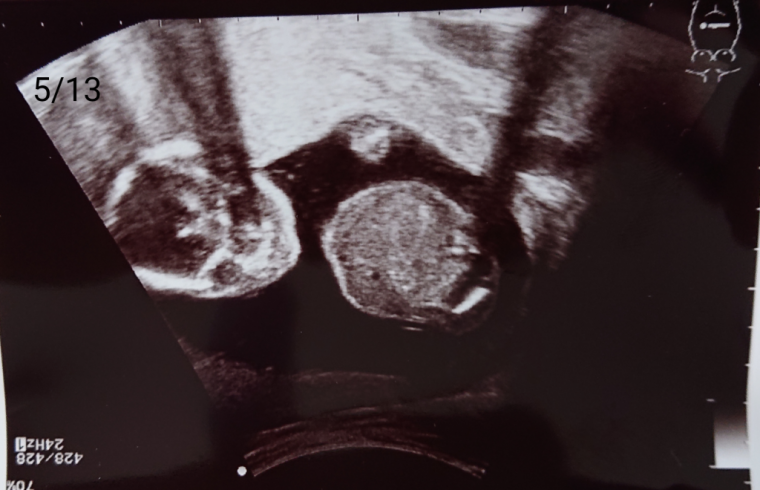

妊娠5ヶ月 妊娠16週,17週,18週,19週,妊娠中期 の超音波写真妊娠・出産・育児に関する総合情報サイト ベビカム。

妊娠5ヶ月 妊娠16週,17週,18週,19週,妊娠中期 の超音波写真妊娠・出産・育児に関する総合情報サイト ベビカム。

妊娠5ヶ月 妊娠16週,17週,18週,19週,妊娠中期 の超音波写真妊娠・出産・育児に関する総合情報サイト ベビカム。

妊娠5ヶ月ベビカム成長記録妊娠・出産・育児に関する総合情報サイト ベビカム。